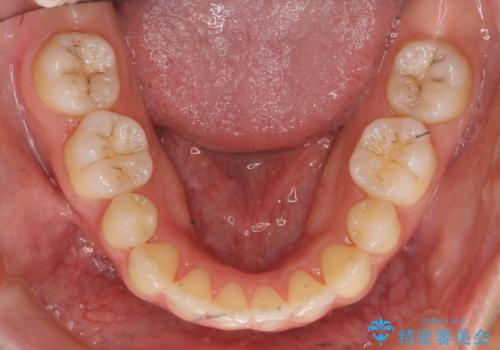

- 小さいころに小臼歯を抜歯しワイヤー矯正をしたが、すき間が空いてきて、前歯の並びが戻ってしまったとのこと。

インビザラインライトという部分矯正コースで、全体矯正に比べ、比較的安価に治療しました。

前歯の並びが格段にきれいになり、大変喜んでいただけました。